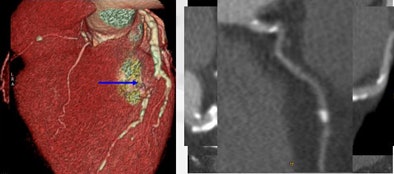

| A diabetic patient with severe, diffuse artery disease encompassing three vessels was difficult to evaluate with 64-detector-row coronary CT angiography. There is occlusion in all segments of the left coronary artery, left circumflex artery, and right coronary artery. Image courtesy of Dr. Daniele Andreini. |